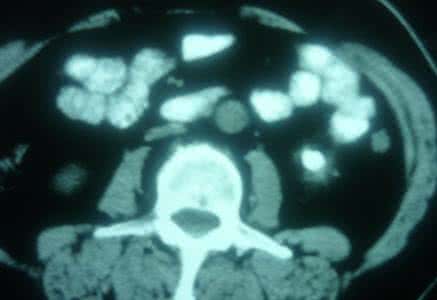

肾结石为泌尿系统常见病,多发病,男性发病多于女性,多发生于青壮年,左右侧的发病率无明显差异。肾结石给人们印象最深刻的是疼痛难忍,而且没有什么理想方法缓解或者预防这种疼痛。肾结石造成的疼痛有多么严重?有资料说疼痛可以分12级,那么肾结石绞痛达到11级,和心绞痛、三叉神经痛和胆道蛔虫疼痛类似,仅次于孕妇分娩。如果患有肾结石,或许可喝一点藤黄果泡茶饮(偏方)。